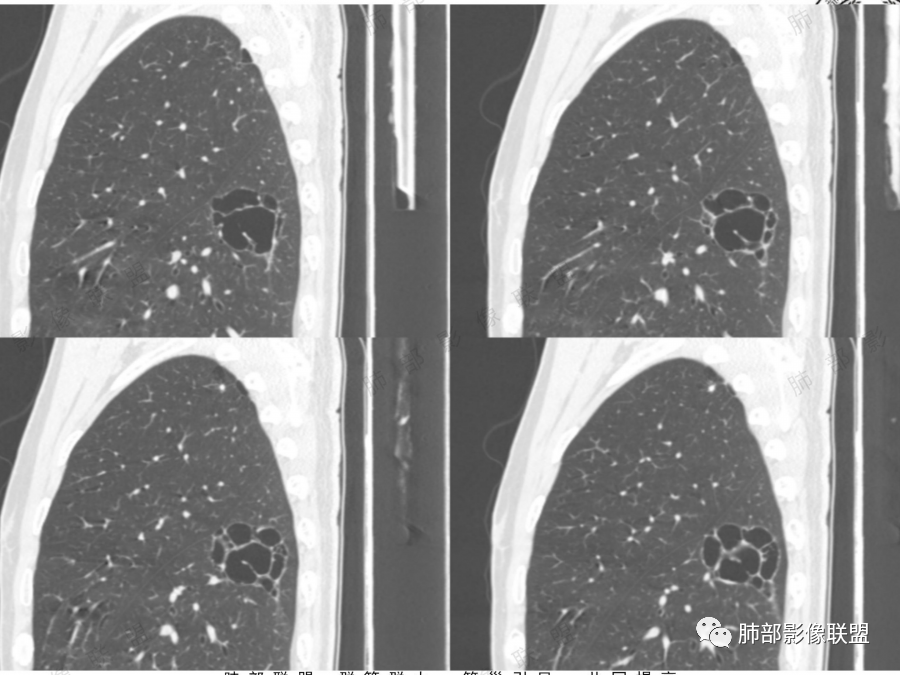

1.囊壁是否规则,内壁是否光整。

2.囊壁是否存在不规则增厚或伴有壁结节。这有时需要薄层冠矢状位观察。应留意壁结节及增厚囊壁有无异常强化。

3.囊腔内结构:囊内如果有分隔、支气管及血管穿行应该考虑空腔,而非空洞,这种需要高度怀疑恶性

4.囊腔周围是否有清楚的磨玻璃影,如果有强烈提示腺癌

5.病灶是否有分叶、毛刺、支气管截断、血管集束征、胸膜凹陷征等周围型肺癌的影像征象。应留意同侧肺门及纵隔有无增大淋巴结。

6.动态随访观察:初期囊腔病灶未出现明显恶性征象时诊断有困难,但是仍要引起足够的重视对病灶密切定期随访,如果随访中囊腔增大、囊壁不规则增厚、壁结节增大、囊腔消失呈实性病灶均应及时手术治疗。

7.影留意是否两肺多发。注意查阅患者既往影像学资料。